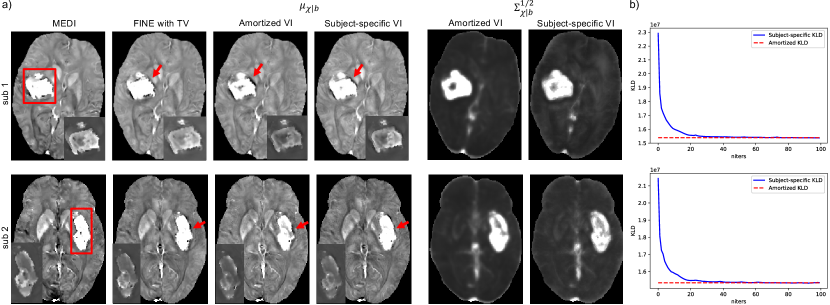

4.5 Amortized vs Subject-specific VI

The inference gap in Eq. 11 was investigated on two ICH test cases shown in Figure 5, where subject-specific VI using Eq. 10 initialized from the weights of PDI was deployed with 100 iterations for convergence. MAP estimations in Eq. 3 of iterative reconstruction MEDI and network parametrized reconstruction FINE with TV (, 100 iterations) were also delpoyed for comparison. As demonstrated in Figure 5a, both amortized and subject-specific VIs recovered the susceptibility value inside the hemorrhage from PDI in Figure 4. Compared to amortized VI, the susceptibility values at the center of hemorrhage (insets in Figure 5a) were further recovered and shadow artifacts surrounding the hemorrhage (red arrows in Figure 5) were reduced in subject-specific VI. In addition, subject-specific VI had similar reconstructions to MEDI and FINE with TV for both test cases, which confirmed that the mean susceptibility map by subject-specific VI equals the MAP susceptibility maps by MEDI and FINE with TV. Figure 5b shows that KL divergence of Eq. 10 during subject-specific VIs converged to the value of amortized VIs with almost zero amortization gap (Eq. 11). Figure 6 shows the value changes of three individual terms in Eq. 10 during subject-specific VI iterations, where the second term () was slightly lower on average than the one of amortized VI for both test cases, which might contribute to the improvement of shadow artifact reduction.

The inference gap (Eq. 11) summarizes two types of errors when applying the amortized inference strategy. Amortized VI has the advantage of fast inference during test time. However, it has slightly worse visual quality inside and surrounding the hemorrhage than subject-specific VI (Figure 5a). Even though an almost zero amortization gap was achieved (Figure 5b), the regularization term of KL divergence (Eq. 10) was still better imposed in subject-specific VI, which may contribute to its better reconstruction of the hemorrhage. However, such advantage comes at a cost of extra inference time. To accelerate the inference speed of subject-specific VI, optimizing the initialization of variational parameters is useful to reduce the number of VI optimization steps. Meta-learning (Naik and Mammone, 1992; Hochreiter et al., 2001) may be applied to optimize the optimization process of VI per data, where a learner can be designed during pre-training to learn an inference algorithm that generalizes well to the data of interest.